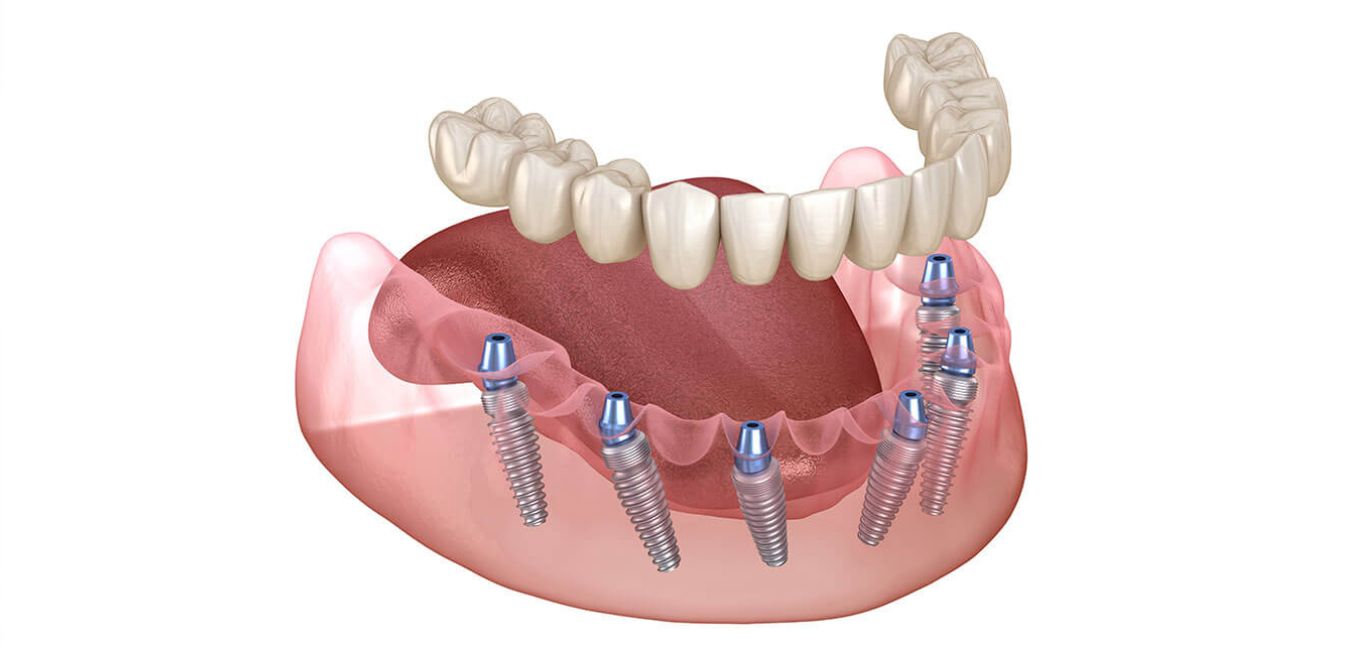

Dental implants are a permanent solution for missing teeth that look, feel, and function just like natural teeth. At Prime Gupta Dental Care Hospital, we use high-quality titanium implants that are securely placed into the jawbone to support artificial teeth such as crowns or bridges.

Implants help restore your smile, improve chewing ability, and prevent bone loss in the jaw. Our skilled dental team ensures a safe, comfortable procedure with long-lasting results, giving you the confidence to eat, speak, and smile without worry.